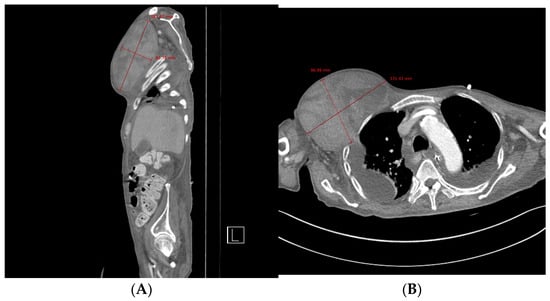

Figure 1. Chest computed tomography. (A) Sagittal view showing the formation of a hematoma measuring approximately 19 × 8 cm. (B) Axial view showing a newly formed 13 × 10 cm hematoma in the right upper anterior chest wall without evidence of active bleeding or pseudoaneurysm.

Chest computed tomography (CT) angiography revealed a newly formed 18.7 × 13.1 × 9.6 cm hematoma in the right upper anterior chest wall, with no signs of active bleeding or evidence of a pseudoaneurysm or malignant tumor (Figure 1 and Figure 2). On the fourth day post-onset, transarterial angiography was conducted via the right common femoral artery. Angiograms of the right subclavian artery, right internal mammary artery, and thoracic aorta showed no active bleeding, precluding the possibility of embolization. To manage the resulting anemia, 2 units of PRCs were transfused.